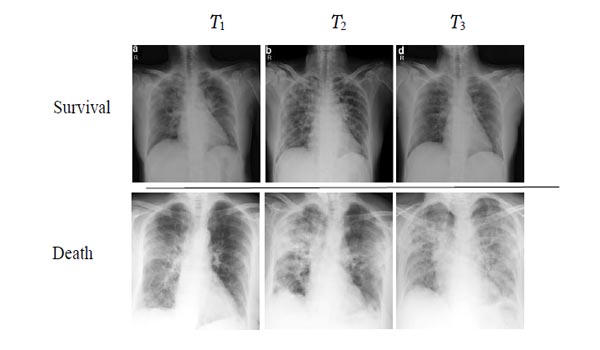

As reported in the previous section, good precision and recall values indicate the ability of our ProgNet architecture to properly classify ambiguous cases. In this sense, Fig. (8) shows two examples of time-series corresponding to two patients with survival and death issues. These patients are well classified by the proposed ProgNet architecture, while the competing methods misclassify them. When visually inspecting the images for the death issue, ambiguity comes from extended white areas in all the images with no visible improvement over time. The same remark holds for the survival case where white areas persist over time.

To investigate why the proposed ProgNet architecture fails to classify some cases, Fig. (9) shows images of a time-series linked to a patient mis-classified by ProgNet. Indeed, we notice, in some cases, an unexpected change in the situation of a patient during the last image of the sequence. This can lead to some problems in learning all features and managing the time correlation between them. Analysing longer sequences can certainly improve model performance.